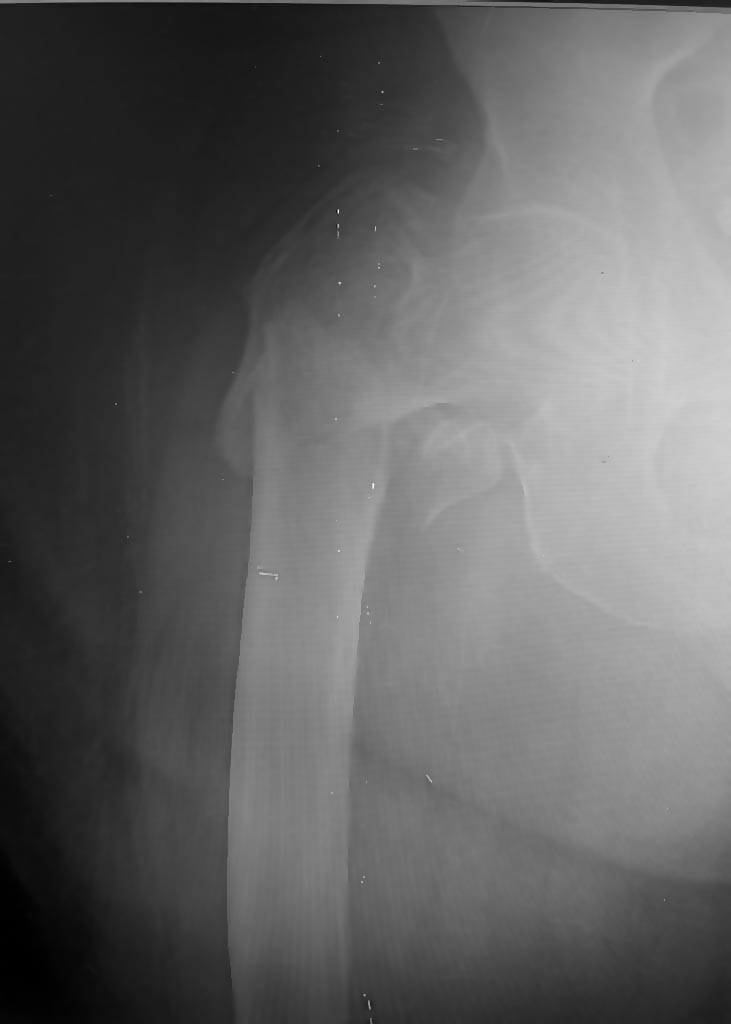

| вверх отправить поиск админ главная | Добрый день, уважаемые коллеги. < синтез или э/протезирование? | The Concise Orthopaedic Revision Notes >